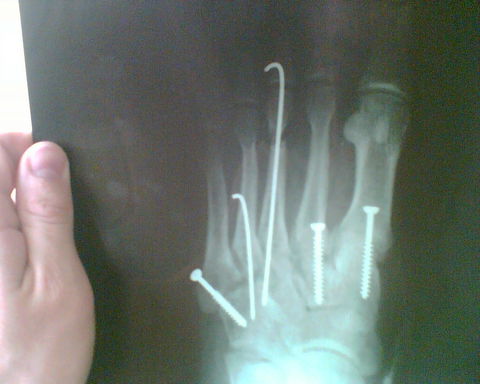

-> pistaa: co si robil? mne sa len 2x podarilo vytknut clenok, ale taky sikovny aby mi to museli srobovat som neni